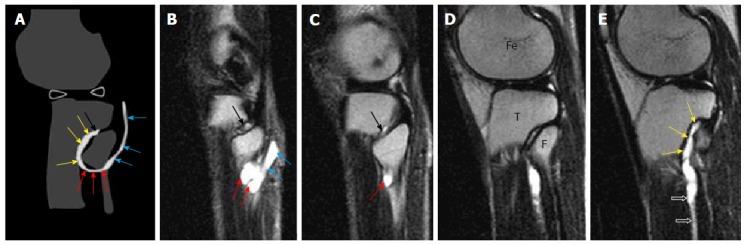

A retrospective analysis of the magnetic resonance (MR) images of a cohort of 245 patients presenting with nerve palsy involving different peripheral nerves was done. MR images were analyzed for the presence of a nerve lesion, and if found, it was further characterized as solid or cystic. The serial axial, coronal and sagittal MR images of the lesions diagnosed as INGC were studied for their pattern and the anatomical extent along the course of the affected nerve and its branches. Its relation to identifiable anatomical landmarks, intra-articular communication and presence of denervation changes in the muscles supplied by involved nerve was also studied.

A total of 45 cystic lesions in the intra or extraneural locations of the nerves were identified from the 245 MR scans done for patients presenting with nerve palsy. Out of these 45 cystic lesions, 13 were diagnosed to have INGC of a peripheral nerve on MRI. The other cystic lesions included extraneural ganglion cyst, paralabral cyst impinging upon the suprascapular nerve, cystic schwannoma and nerve abscesses related to Hansen's disease involving various peripheral nerves. Thirteen lesions of INGC were identified in 12 patients. Seven of these affected the common peroneal nerve with one patient having a bilateral involvement. Two lesions each were noted in the tibial and suprascapular nerves, and one each in the obturator and proximal sciatic nerve. An intra-articular connection along the articular branch was demonstrated in 12 out of 13 lesions. Varying stages of denervation atrophy of the supplied muscles of the affected nerves were seen in 7 cases. Out of these 13 lesions in 12 patients, 6 underwent surgery.